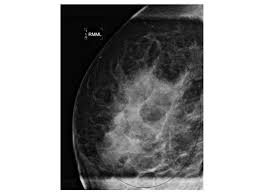

What Does Margins Mean In Cancer / Reading A Pathology Report Cancer Net - It will usually contain the type of cancer, tumor grade, lymph node status, margin status, and stage.. There is no strict guideline for exactly how wide the margin around a tumor should be. If cancer cells are present, this will influence decisions about treatments such as additional surgery and radiation. Usually notes about samples that have been sent for other tests or a second opinion Global asymmetry, focal asymmetry, developing asymmetry when there is asymmetric density on a mammogram image, it can mean that a mass is developing, but it is far more likely that it is something else. A positive margin means that cancer cells come right out to the edge of the removed tissue and have ink on them.

Positive margins mean that cancer cells are found at the edge of the material removed negative, not involved, clear, or free margins mean that no cancer cells are found at the outer edge close margins are neither negative nor positive other information: A positive or involved margin means there are cancer cells in the margin. Margins help show whether or not all of the tumor was removed. One can think of this situation as removing an orange where the peel is the capsule of the prostate and the fruit is the cancer. The mean age at diagnosis was 66 years, with a median age of 67 and range of 28 to 87 years. But having a positive margin does not necessarily mean that a patient's cancer is going to recur, even if he doesn't have radiation therapy. New evidence about why clear margins in breast cancer surgery are such good news date: This rim is called a margin. Negative margins mean a small amount of normal tissue around the entire tumor was also removed and is free of cancer cells—this ensures the entire melanoma is removed. The report will describe the location of the tumor to the margins, or edges of the biopsy or tissue sample. Global asymmetry, focal asymmetry, developing asymmetry when there is asymmetric density on a mammogram image, it can mean that a mass is developing, but it is far more likely that it is something else. Medical college of georgia at augusta university Negative/not involved/clear margins mean that no cancer cells are found at the outer edge.

Pdf Margin Analysis In Head And Neck Cancer State Of The Art And Future Directions Semantic Scholar from d3i71xaburhd42.cloudfront.net Many many pages of information later we found that every surgeon has a different definition of what a clean margin is! These findings suggest that in the case of pancreatic cancer, a margin clearance of 1.5 mm would be a useful definitionof r1 in both a clinical and a trial setting. Negative and close margins:when margins are ink. During or after surgery, a pathologist examines this rim of tissue — called the surgical margin or margin of resection — to be sure it's clear of any cancer cells. Global asymmetry, focal asymmetry, developing asymmetry when there is asymmetric density on a mammogram image, it can mean that a mass is developing, but it is far more likely that it is something else. After the procedure, a pathologist examines the removed tissue to check for remaining cancer cells in the lumpectomy margins. But having a positive margin does not necessarily mean that a patient's cancer is going to recur, even if he doesn't have radiation therapy. This means that it is likely that cancerous cells are still in the body.